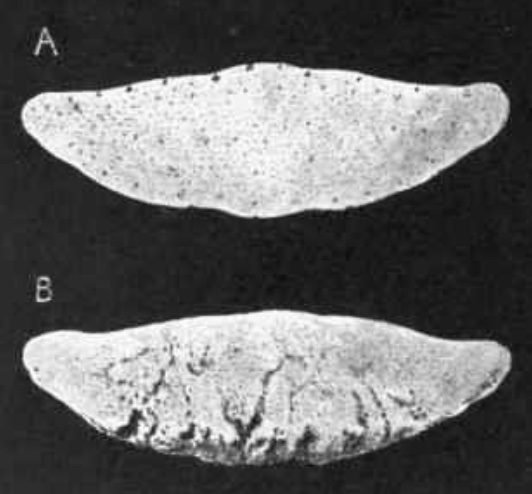

what is this

a- normal

b- navicular dz w/ synovial invaginations (lollipops)